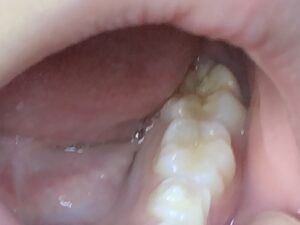

臼井家の5年生の長女<Hカ>の第一大臼歯は、6歳頃に生えてきた時点で、噛む面(咬合面)が黄白色をしていて、正に<エナメル質形成不全>を生じていました。

乳歯や他の永久歯には問題がなく、左右の第一大臼歯だけ同じような状態だったことから、やはりお腹の中にいて第一大臼歯のエナメル質が形成される時期(多くの場合左右の同じ歯は同じ頃に形成されています)に、何かしらの問題が生じていたことが考えられますが、